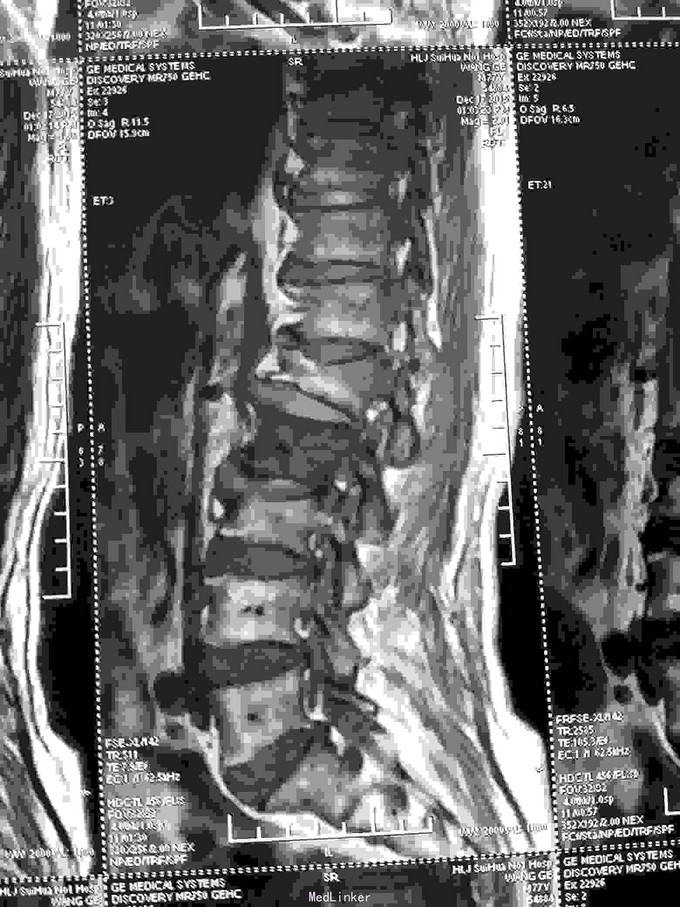

根据病史查体诊断:腰间盘突出症待确诊。应用消肿营养神经镇痛治疗。一天。查核磁共振示:腰椎多节段间盘突出伴椎管狭窄。第二腰椎骨破坏侵及椎板。部分突入椎管,脊髓受压。诊断:腰间盘突出伴椎管狭窄。第二腰椎转移癌,脊髓受压。经与家属沟通,查双肺CT:双肺下叶炎症。肺部纤维化。可见肿瘤阴影。肋骨及胸膜受累。胸椎部分骨破坏。最终诊断:双肺癌,胸椎,腰椎骨转移,脊髓受压。多节段腰椎间盘突出。病人至肿瘤科治疗。